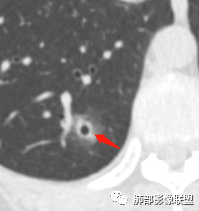

横断位看上去晕很模糊,冠矢状位重建后却比较清晰,所以单次CT检查蛮难定的,中心透亮区一定是空洞吗?我怎么觉得是一支气管壁有增厚,管腔有轻度扩张的支气管,第一感觉还是炎性结节吧,PC可能大,一定要否定腺癌也不敢,一个月左右复查。

连续层面显示这个应该是空泡,或者小空洞,远端没有,近端也没有,周围环形软组织增厚。而空泡,影像上只是根据5mm界线,病理上不一定。

问一个问题,肺动脉肺静脉?为啥?

生来征服~浪子:

静脉,夹角90,周边没气管伴行。

果哣.:

静脉吧,动脉同时会伴有一根气管

南边:

这些呢?为啥?

宇宙星空:

动脉,有支气管伴行

伴有支气管

假如这是含气支气管,伴随的哪条动脉呢?近端从哪来?为啥环形壁增厚而又不均匀?都不太符合,所以支持空泡或小空洞。